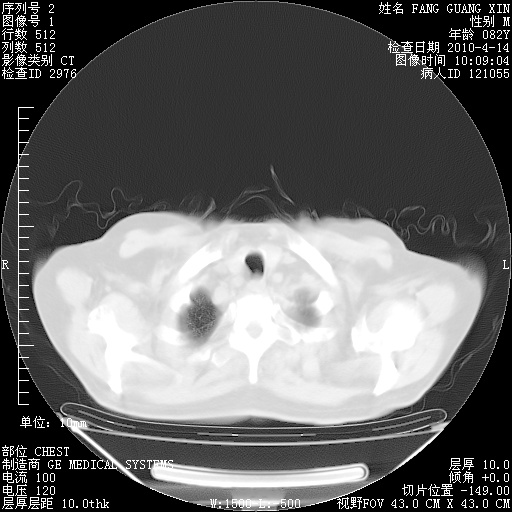

4月14日肺部CT

楼主| 发表于 2010-4-28 16:51 | 显示全部楼层

楼主| 发表于 2010-4-28 16:53 | 显示全部楼层

肺部CT平扫未见异常。